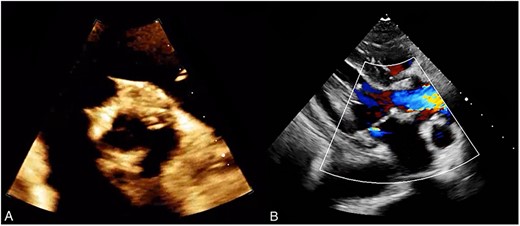

The patient had an uncomplicated postoperative course in the intensive care unit and was then shifted to the surgical step-down unit. However, the patient developed a superficial sternal wound infection, which was managed with the use of a vacuum-assisted closure (VAC) device. Once the wound had healed, it was closed under general anesthesia with an incisional VAC device installation. After 3 months, the patient underwent a follow-up transthoracic echocardiogram (TTE), which showed a normally functioning aortic valve prosthesis with normal global left ventricular function (Fig. 3).

(A) Post operative TTE demonstrating a bioprosthetic valve in proper position. (B) Normal functioning bioprosthetic aortic valve with no signs of stenosis or regurgitation.